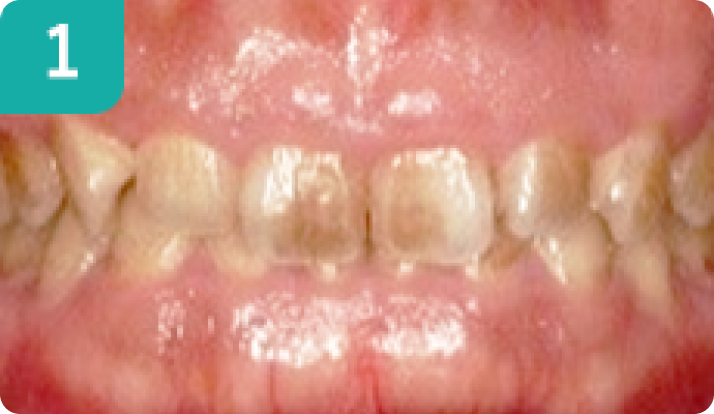

歯肉整形 8本

上前歯が小さいのとガミースマイルを歯肉整形にて改善しました。上前歯の縦長さが短めで歯が小さく見えて歯肉ラインが不揃いでした。歯肉整形をすることで、口元からの歯の見え方が整ってスマイル時の印象が良くなりました。

【治療期間】2週間 【費用】80,000円(税別) 【リスク・副作用】術後2~5日程は傷口に赤みが見えたり、痛みが生じる場合があります。当院で行う歯肉整形は歯と歯肉、歯槽骨に対して行う処置であり、入院が必要な骨切り手術(Le Fort手術)などは対応していません。